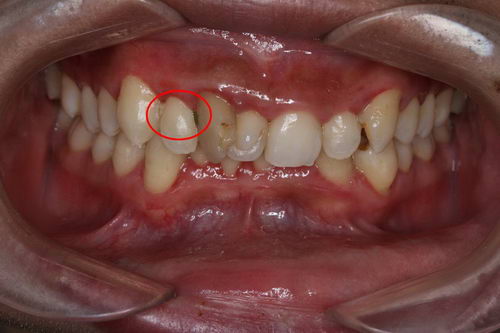

这是一位戴固定矫正装置的患者

图中牙面上的红色是通过一种染色剂标记的牙齿表面软垢的位置。第一张可以明显看到如果简单清洁,很多细节部位是清洁不到的。

第二张,这是仔细清洁之后的效果,但仍能能看到牙齿仍然有部分没刷干净的位置。像这种刷牙时有阻挡物的情况,如果不通过“穿针引线”式的清洁操作,牙缝根本就没法刷干净。

第三张是使用邻面清洁工具之后,基本上是已经清洁干净了。